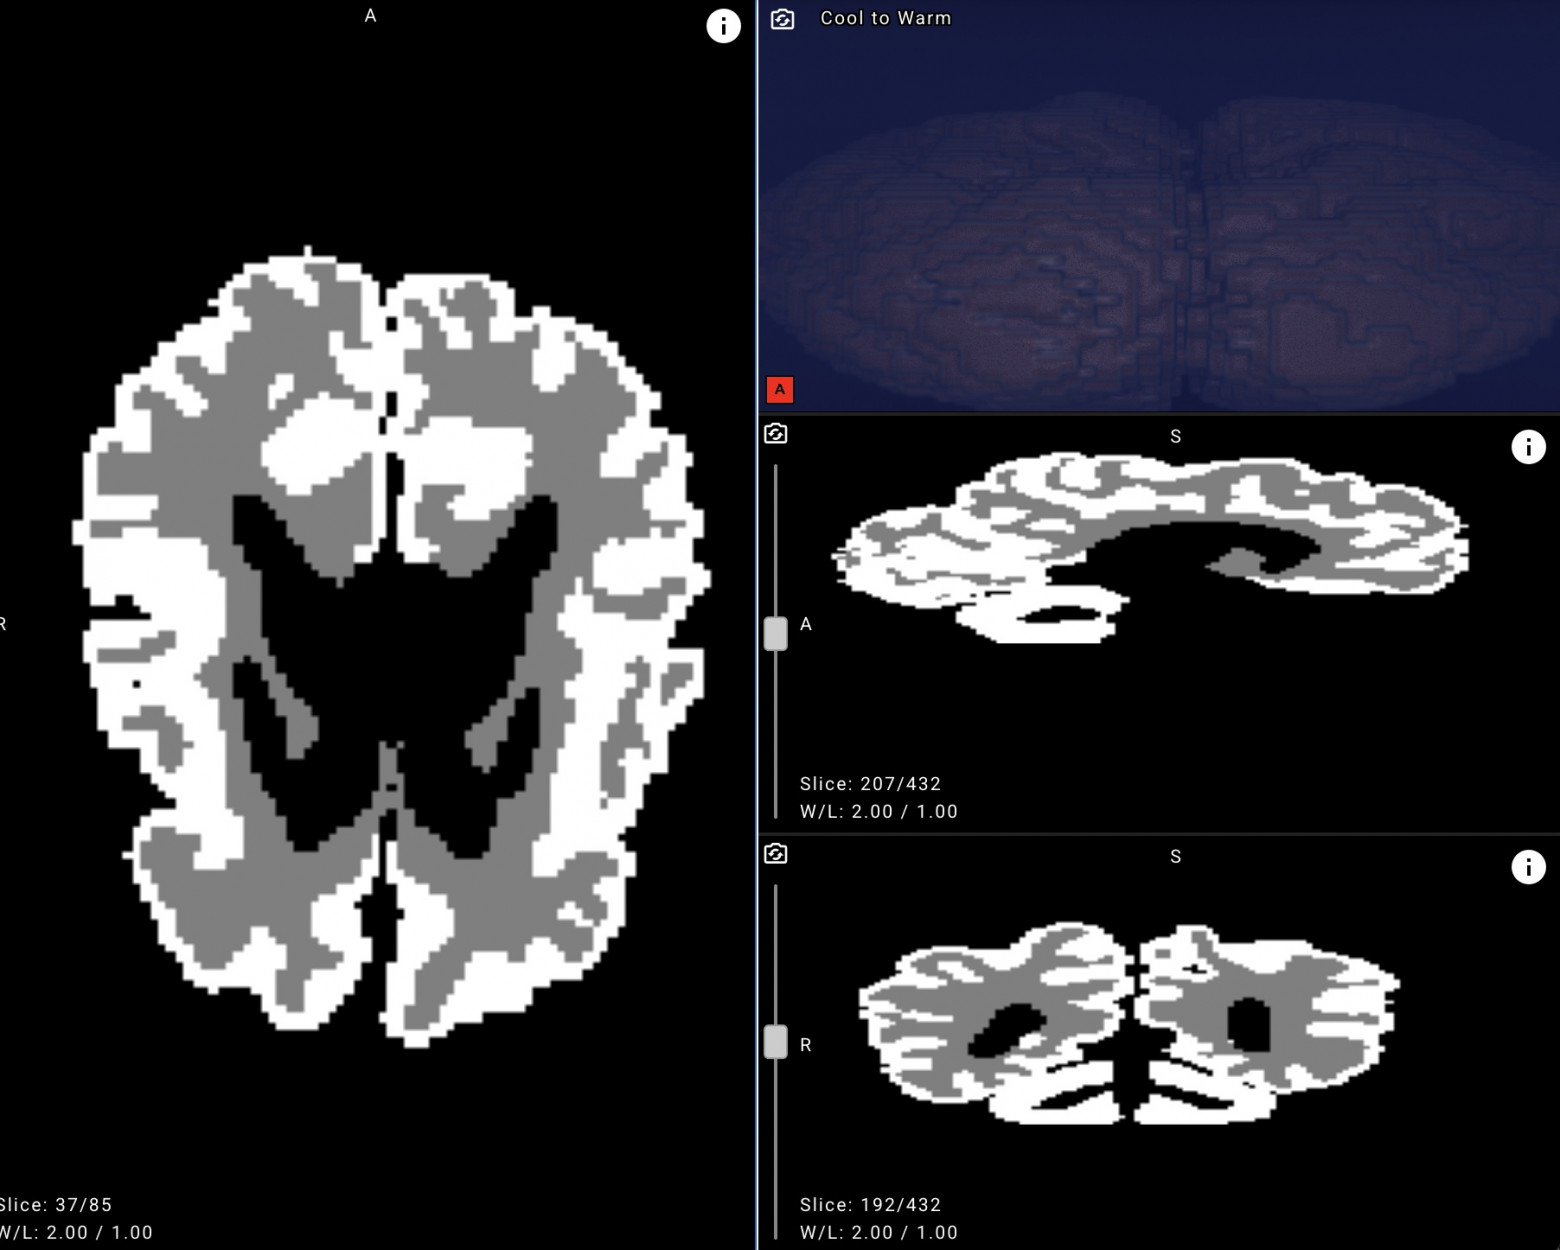

Сервис работает на платформе Yandex Cloud и анализирует результаты МРТ мозга младенцев. Система автоматически размечает снимки и вычисляет объёмы белого и серого вещества. Решение сокращает время анализа результатов с нескольких дней до пары минут. Это помогает врачам ускорить диагностику и лечение ДЦП, а также других заболеваний центральной нервной системы новорождённых. По словам разработчиков, это ИИ‑решение — первое в мире для диагностики пациентов столь раннего возраста.

Модели и алгоритм обучения доступны разработчикам на платформах SourceCraft и GitHub. Врачи могут использовать нейросеть в формате веб‑сервиса. Технология отличается высокой точностью сегментации белого и серого вещества — свыше 90%. Скорость обработки одного снимка составляет около 3 секунд. Ранее Центр технологий для общества Yandex Cloud выложил в открытый доступ нейросеть для ранней диагностики spina bifida — редкого заболевания центральной нервной системы.